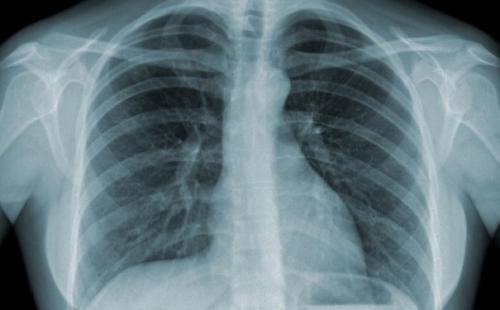

(Ngày Nay) - Các nhà khoa học tại Phòng thí nghiệm Bệnh truyền nhiễm A*STAR (A*STAR IDL) đã phát hiện ra phương thức các cấu trúc hình thành trong phổi trong quá trình nhiễm lao, được gọi là u lao, có thể tạo môi trường thuận lợi cho bệnh viêm phổi thứ phát phát triển. Phát hiện này giải thích lý do tại sao một số người rất dễ bị viêm phổi thứ phát sau khi đã điều trị bệnh lao thành công.

Các nhà khoa học cho biết bệnh lao có thể dẫn đến những thay đổi lâu dài trong phổi, làm tăng nguy cơ viêm phổi thứ phát, bao gồm cả viêm nhiễm do vi khuẩn mycobacteria không lao (NTM). Tình trạng viêm nhiễm do NTM gây ra, chẳng hạn như vi khuẩn Mycobacterium abscessus, đã gia tăng tại Singapore và nhiều quốc gia khác trong nhiều thập kỷ. Khi nghiên cứu, các nhà khoa học phát hiện các u lao (có thể được phát hiện thông qua sàng lọc bằng tia X) có thể hoạt động như một môi trường bảo vệ cho vi khuẩn thứ phát. Cụ thể, Mycobacterium abscessus nhanh chóng xâm chiếm các u lao đã tồn tại từ trước. Một khi đã ở bên trong các cấu trúc này, vi khuẩn được bảo vệ khỏi hệ thống miễn dịch và ít nhạy cảm hơn với thuốc kháng sinh. Ngược lại, vi khuẩn nằm bên ngoài u lao nhanh chóng bị khống chế và loại bỏ.

Nghiên cứu sâu hơn đã tiết lộ cách Mycobacterium abscessus thích nghi với môi trường khắc nghiệt này, bằng cách ăn các mô hoại tử được tìm thấy ở nhân của u lao. Một khi đã hình thành, viêm nhiễm thứ phát có thể phát triển nhanh hơn so với bệnh lao phổi ban đầu.

Phát hiện này cho thấy chỉ loại bỏ lao phổi thôi có thể là chưa đủ nếu u lao vẫn tồn tại và phổi không lành hoàn toàn. Các tổn thương phổi liên quan đến bệnh lao có thể tạo ra môi trường bảo vệ vi khuẩn phát triển. Tiến sĩ Caroline Choong, Giám đốc lâm sàng của Trung tâm Chăm sóc Lao Quốc gia tại Bệnh viện Tan Tock Seng, cho biết nghiên cứu này củng cố tầm quan trọng của việc đánh giá toàn diện hơn quá trình điều trị bệnh lao. Nhiều bệnh nhân lao vẫn còn sẹo và tổn thương tồn dư trong phổi hậu điều trị, vì vậy, cần theo dõi và giám sát, phòng ngừa và can thiệp sớm để ngăn chặn nguy cơ tái nhiễm dưới bất kỳ hình thức nào.